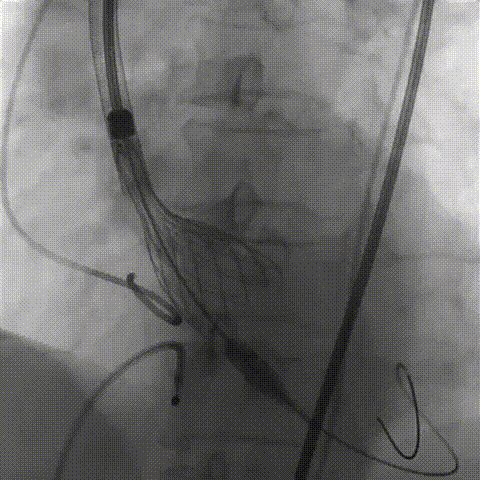

左侧作为主入路置入大鞘

主动脉根部造影

输送器柔顺过弓、跨瓣